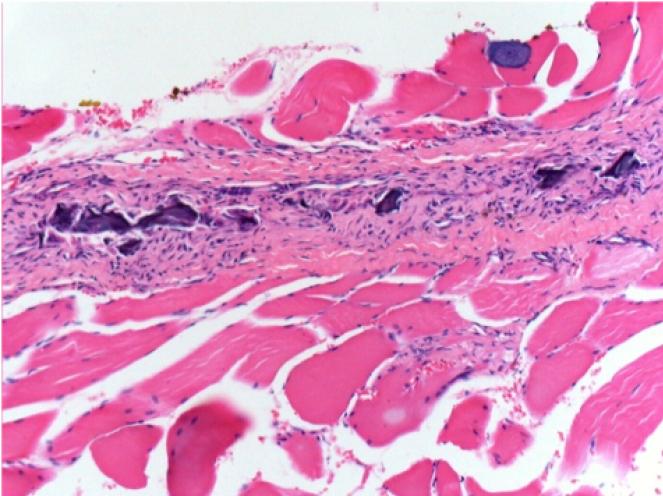

بعد 10 أيام من حقن إندوبيل

10 أيام بعد حقن إندوبيل 0.1 مل في العضلة أمام الظنبوب الأيمن.

هنا قد ترى تشكيل الفجوات التي تحيط بها الخلايا اللمفاوية. الفجوات تختلف عن نخر الأنسجة. يرتبط وجود الخلايا اللمفاوية بنفاذية أغشية الخلايا.

L : Control-100xD10

R:100xD10

R :200xD10

R :400xD10